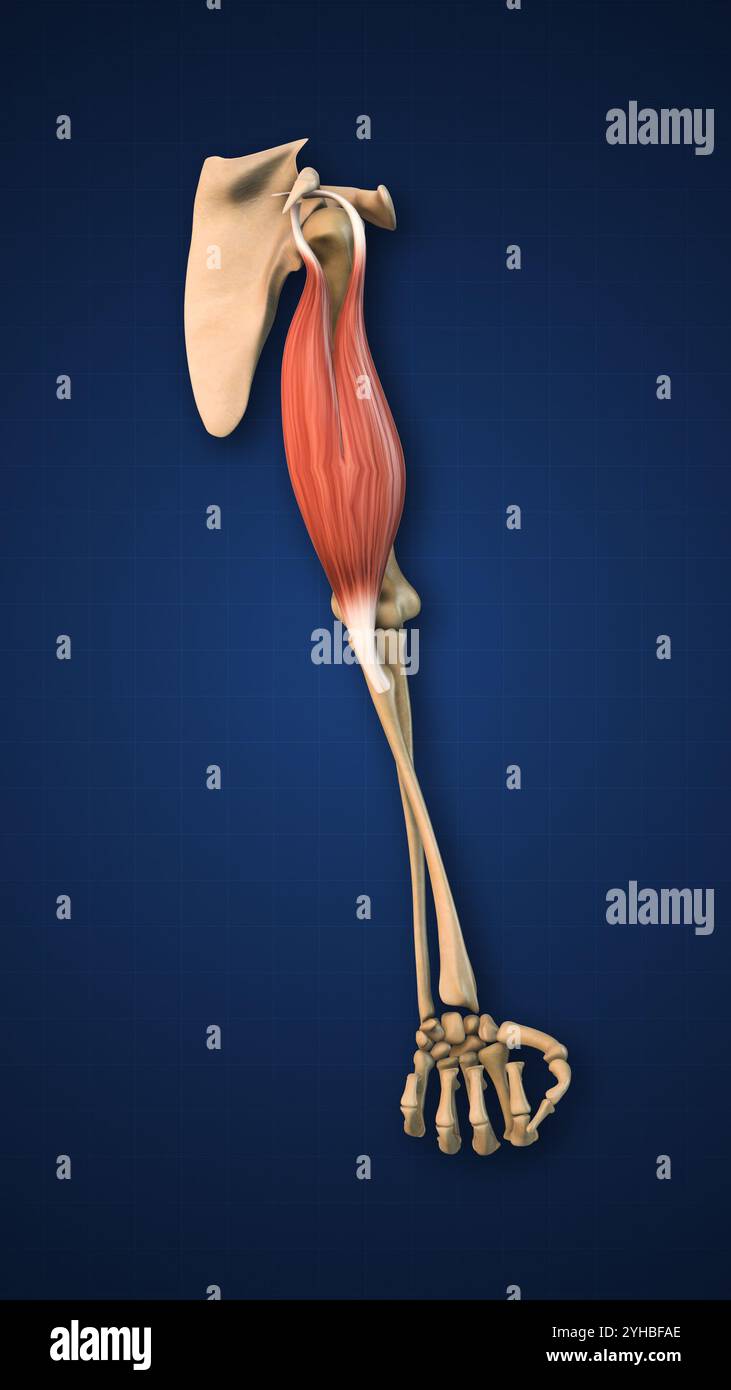

RF3CM31GP–3D-Illustrationskonzept der Anatomie der Knochengelenke der oberen Extremitäten des menschlichen Skelettsystems

RF3CM2YY5–3D-Illustrationskonzept der Anatomie der Knochengelenke der oberen Extremitäten des menschlichen Skelettsystems